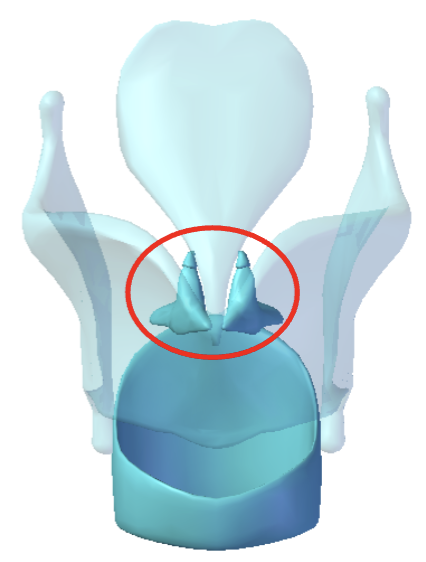

Arytenoid cartilages

Corniculate cartilages

Cuneiform cartilages